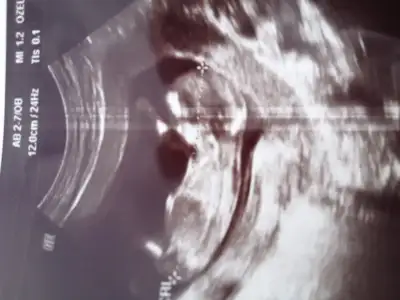

Net deil ama erken bak bi yukarfaki resimde 11 hafta ama cok netKizlar benm bebisime de yorum yapar misiniz dr ikili taramada solemedi tahminini merak ediyorum :)11+4burda Eki Görüntüle 1454687 Eki Görüntüle 1454687

Ama erkege benziyoKizlar benm bebisime de yorum yapar misiniz dr ikili taramada solemedi tahminini merak ediyorum :)11+4burda Eki Görüntüle 1454687 Eki Görüntüle 1454687